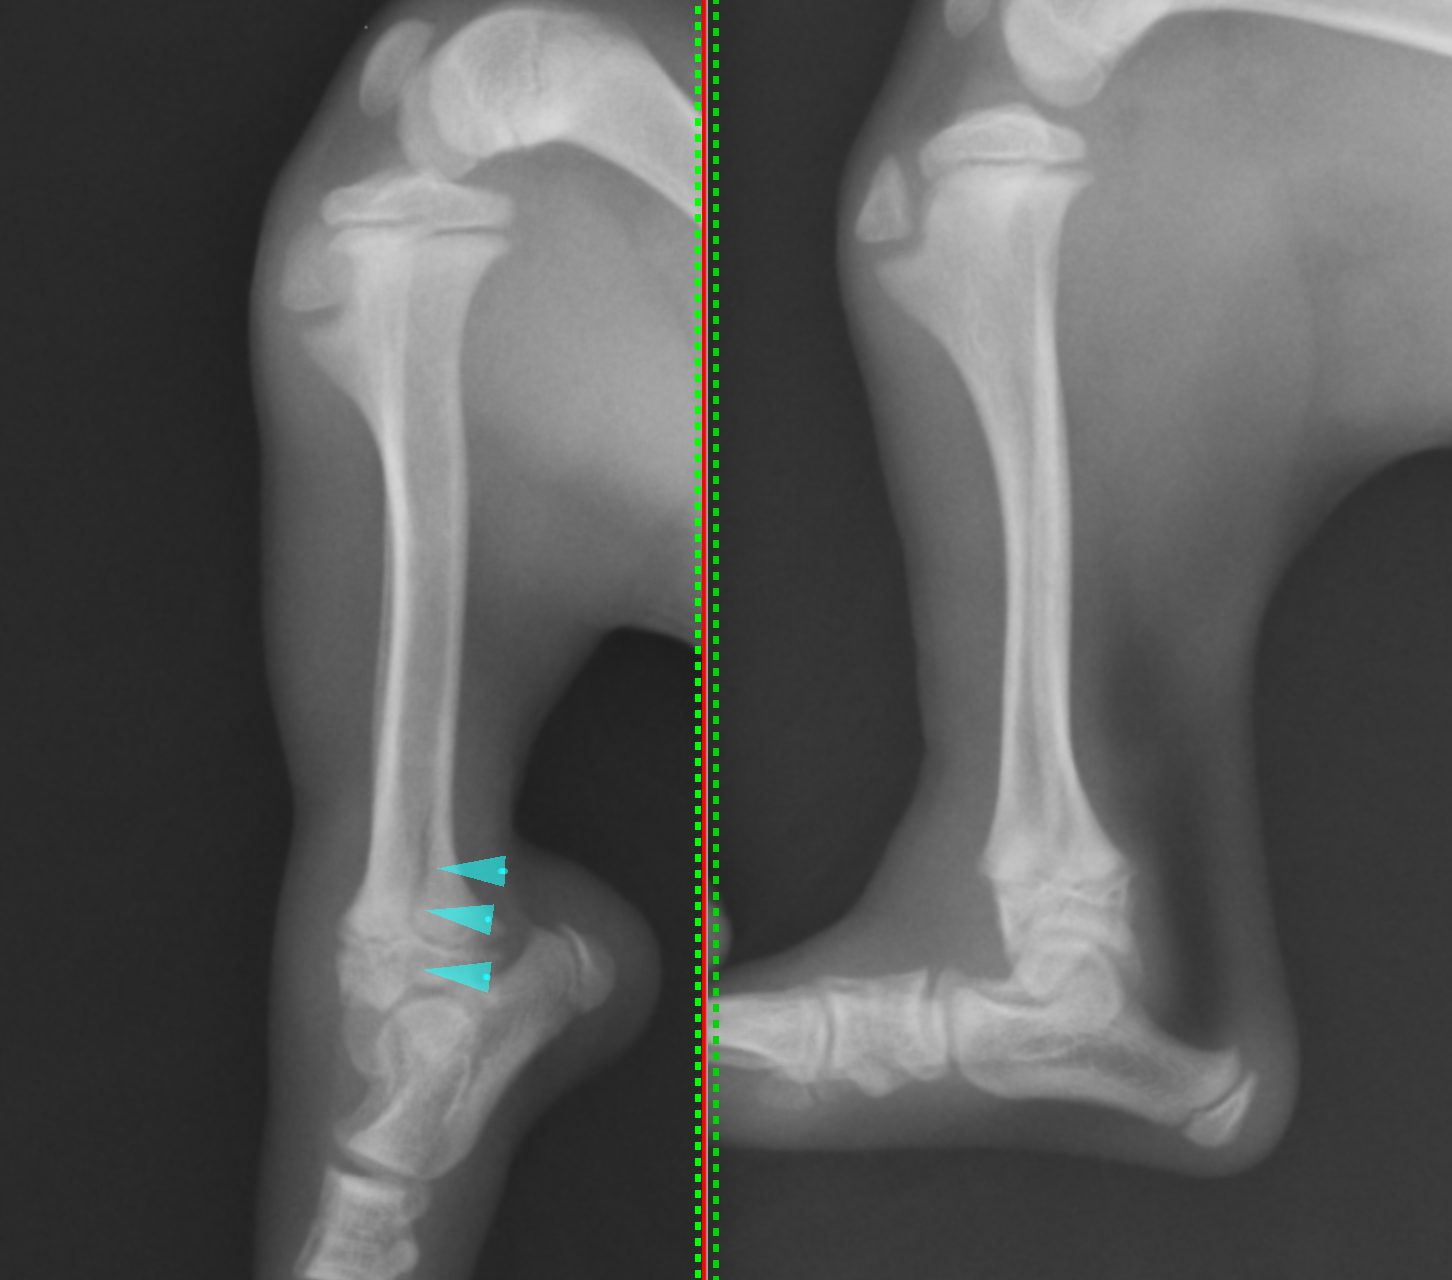

左がストレス撮影したレントゲン画像です。青矢印の部分に亀裂が入っているのが確認されました。成長板をまたいで骨折しており、サルターハリス型骨折のタイプⅣであると診断しました。この子は不幸中の幸いで、完全に骨折したわけではなく、若木骨折という状態で一部はまだくっついている状態でした。

関節を曲げ伸ばしした際に常に痛みがでている、放っておくと成長がうまくできなくなる、若木骨折が完全骨折になるなどを考慮し、すぐに手術することとなりました。サルターハリス骨折の場合には関節面をピッタリと合わせることが重要となります。